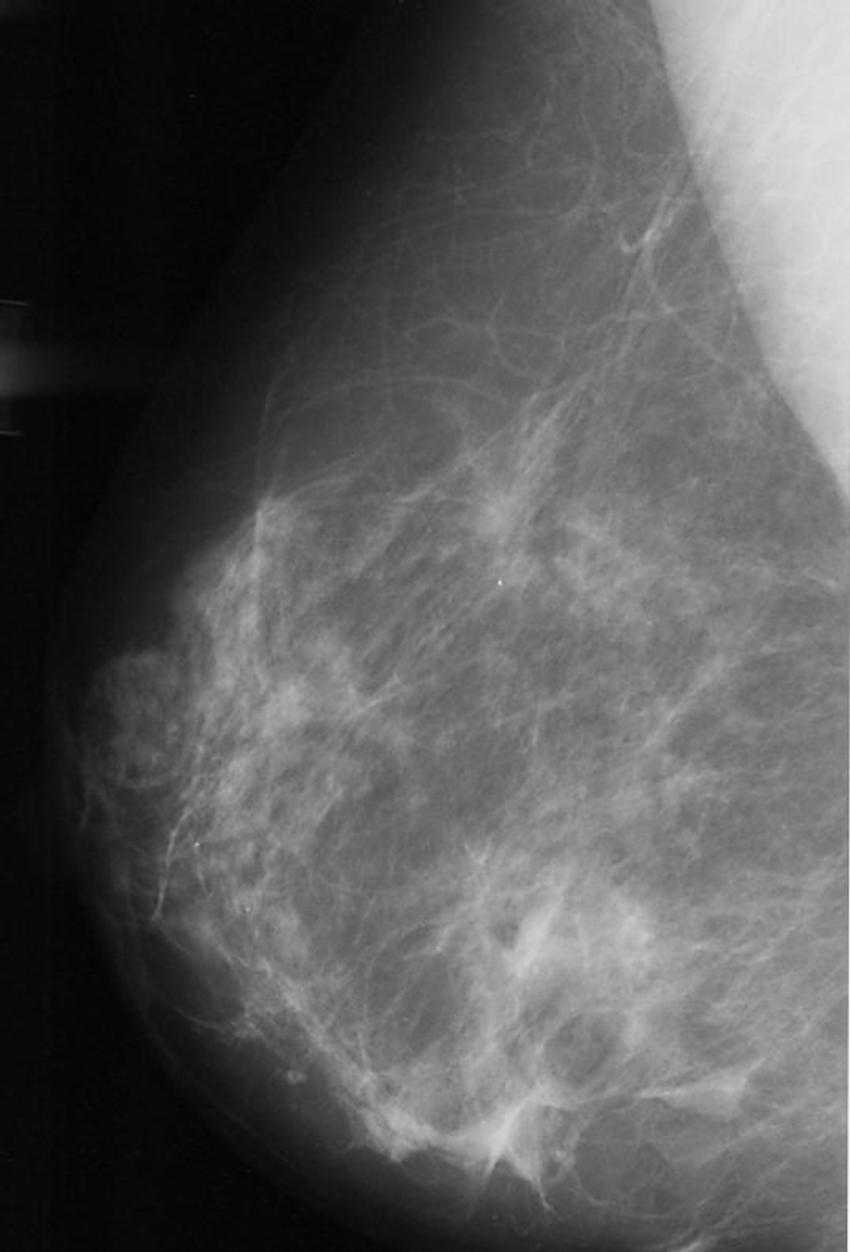

Figure 9. Normal mammogram.